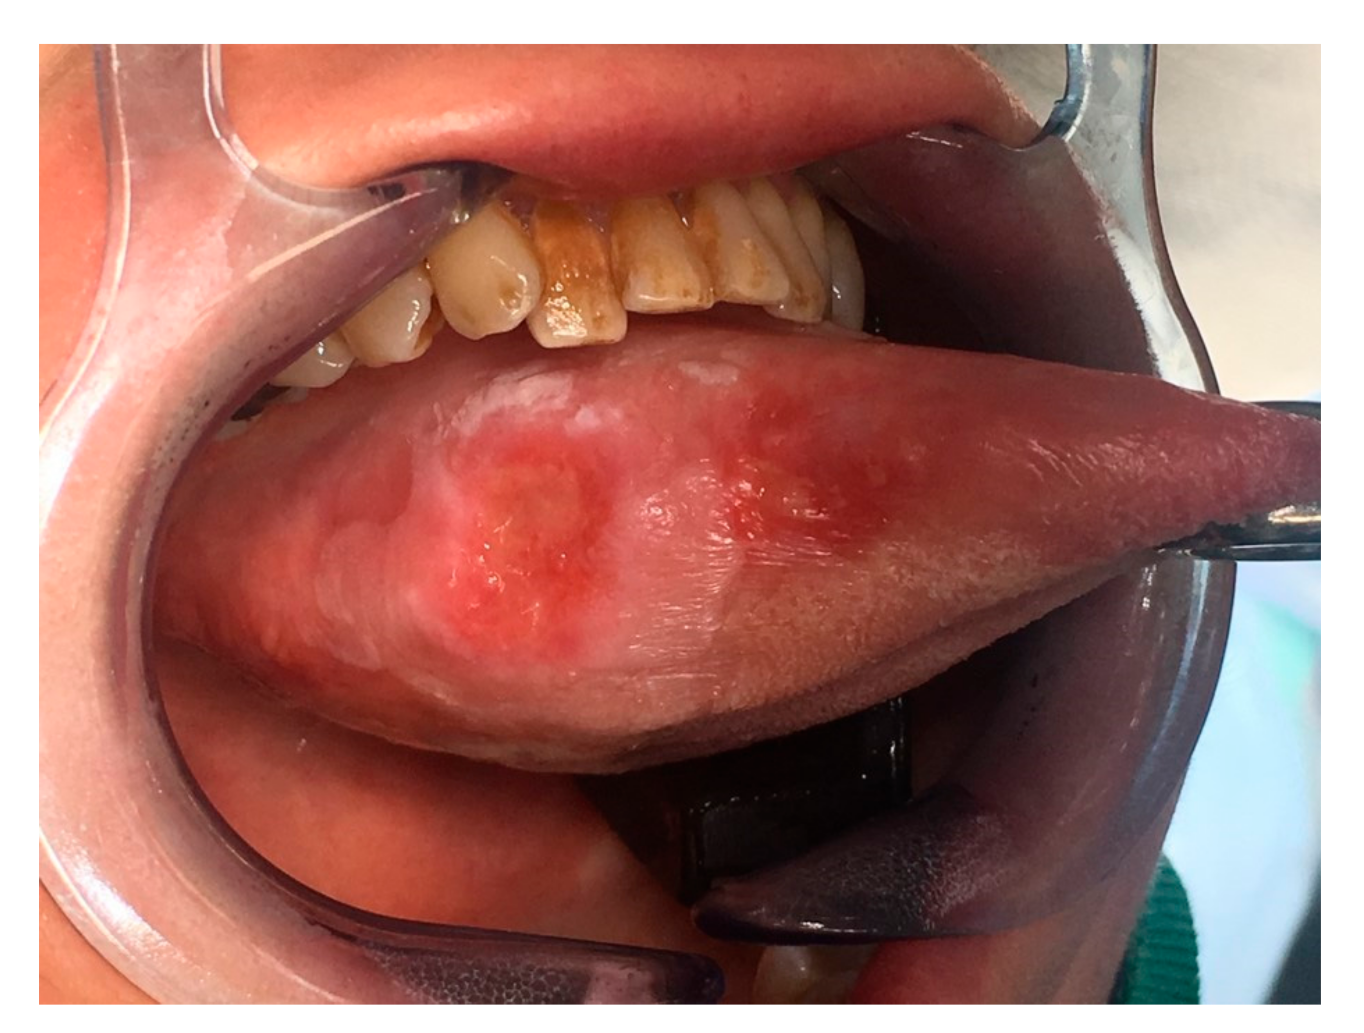

A 53-year-old female was diagnosed with a p16-negative T3N2bM0, Stage IVa SCC of the mobile tongue at an outside institution (Figure 2 and Figure 3). Hemiglossectomy was performed in conjunction with neck dissection of levels I, IIa, III, and IV on the right side. Anterolateral thigh microvascular flap was utilized in reconstruction. Histopathology revealed an SCC with a diameter of 24 mm and with 10 mm depth of invasion. The minimum resection margin was 7 mm on the medial edge of the tumor. She had two metastatic lymph nodes in level IIa with no extranodal extension. The pathological staging was pT2pN2bM0 (Stage IVa). MDTB recommended postoperative chemoradiotherapy.

Figure 2.

Preoperative image of Case 2 showing squamous cell carcinoma of the right mobile tongue.